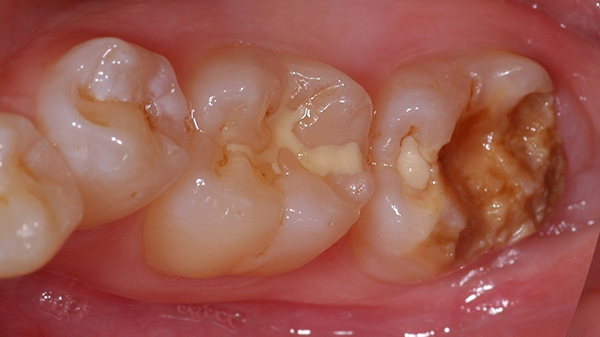

Il Case-Report in questione descrive il trattamento di una giovane paziente che si presenta all'osservazione clinica a causa del disfacimento superficiale della superficie masticatoria del secondo molare inferiore di destra. ( 4.7 )

La peculiarità di questo caso clinico risiede nel fatto che l'amelogenesi imperfetta ha interessato un solo elemento dentale del cavo orale e solo parzialmente lo spessore dello smalto del dente in questione.

All'anamnesi dentale la paziente riferisce che l'elemento dentale in posizione 4.7 si è sempre presentato, rispetto agli altri elementi dentali dei settori posteriori, di colore più scuro tendente al brunastro ma che comunque aveva mantenuto, sostanzialmente, nel tempo le proprie caratteristiche anatomiche e la funzione masticatoria originale.

All'esame obiettivo, l'elemento dentale in questione presenta un'abbondante perdita di sostanza dentale interessante quasi interamente la superficie occlusale e vestibolare ed evidenzia un colore marrone-brunastro nelle parti profonde disgregate mentre un aspetto di smalto normale nella porzione mesiale del dente.

La consistenza al sondaggio di tale tessuto alterato nella colorazione appare dura e non sono presenti segni di rammollimento dovuto all'instaurarsi di patologia cariosa ma piuttosto un progressivo sfaldamento dovuto a distacchi coesivi di porzioni di smalto affetto da amelogenesi imperfetta congenita.

La patologia non ha interessato in toto tutto lo smalto dell'elemento dentario.